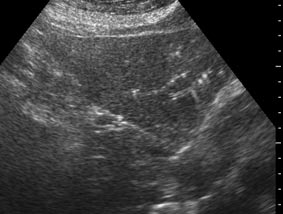

Привожу еще один пример.

Женщина 70 лет,15 лет назад проведена холецистэктомия. Жалобы на боли в эпигастрии.

Наиболее вероятные варианты: хронический холангит, мелкие конкременты внутрипеченочных желчных протоков, холестероз.

на некоторый картинках - действительно - мелкие конкременты желчных ходов,

на других - просто перифокальные изменения стенок сосудов.

такие реактивные изменения печени ВСЕГДА определяются у детей-злостных ацетонщиков до 7 лет - на фоне общего равномерного снижения эхогенности печеночной ткани отмечаются включения повышенной эхогенности линейной и точечной формы.